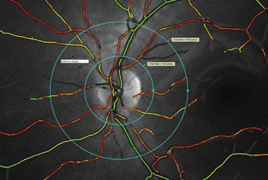

Automatic Retinal Oximetry in Patients with Diabetic Retinopathy

Aim: To determine if oxygen saturation in retinal vessels depends on the degree of diabetic retinopathy.

Material and methods: A prospective study comparing values of oxygen saturation in retinal arteries, veins, and arterio – venous (A-V) difference in healthy persons and in patients with diagnosed diabetes. The study included 114 eyes of 76 patients with diagnosed diabetes, and 57 eyes of 57 patients without diabetes as a control group.

Results: The average retinal arterial saturation in patients without diabetes was 96.5 ± 2.6 %, and increased in patients with severe non-proliferative or proliferative diabetic retinopathy to 100.5 ± 5.6 %. The average venous saturation in patients without diabetes was 62.3 ± 7.4 % and increased to 74,0 ± 7.2 % in patients with severe non-proliferative diabetic retinopathy.

Conclusion: In patients with diabetic retinopathy, we confirmed the increase of hemoglobin oxygen saturation as in the arterial as in the venous blood in retinal vessels; and significant decrease of arterio-venous difference according to the severity of diabetic involvement was confirmed as well.